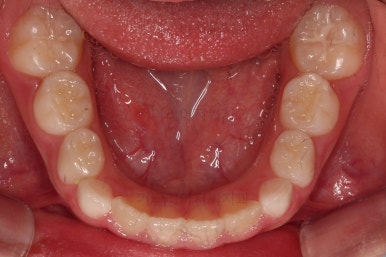

1. 초진

부산어린이교정 키다리아저씨치과에 처음 내원했을 당시의 입안의 모습입니다.

앞니가 거꾸로 물리는 전형적인 앵글씨 3급 부정교합 환아의 모습이었습니다.

아직 유치가 많이 남아 있었꼬, 아래 앞니는 4개가 영구치 맹출, 윗니는 2개가 영구치 맹출 상태였습니다.